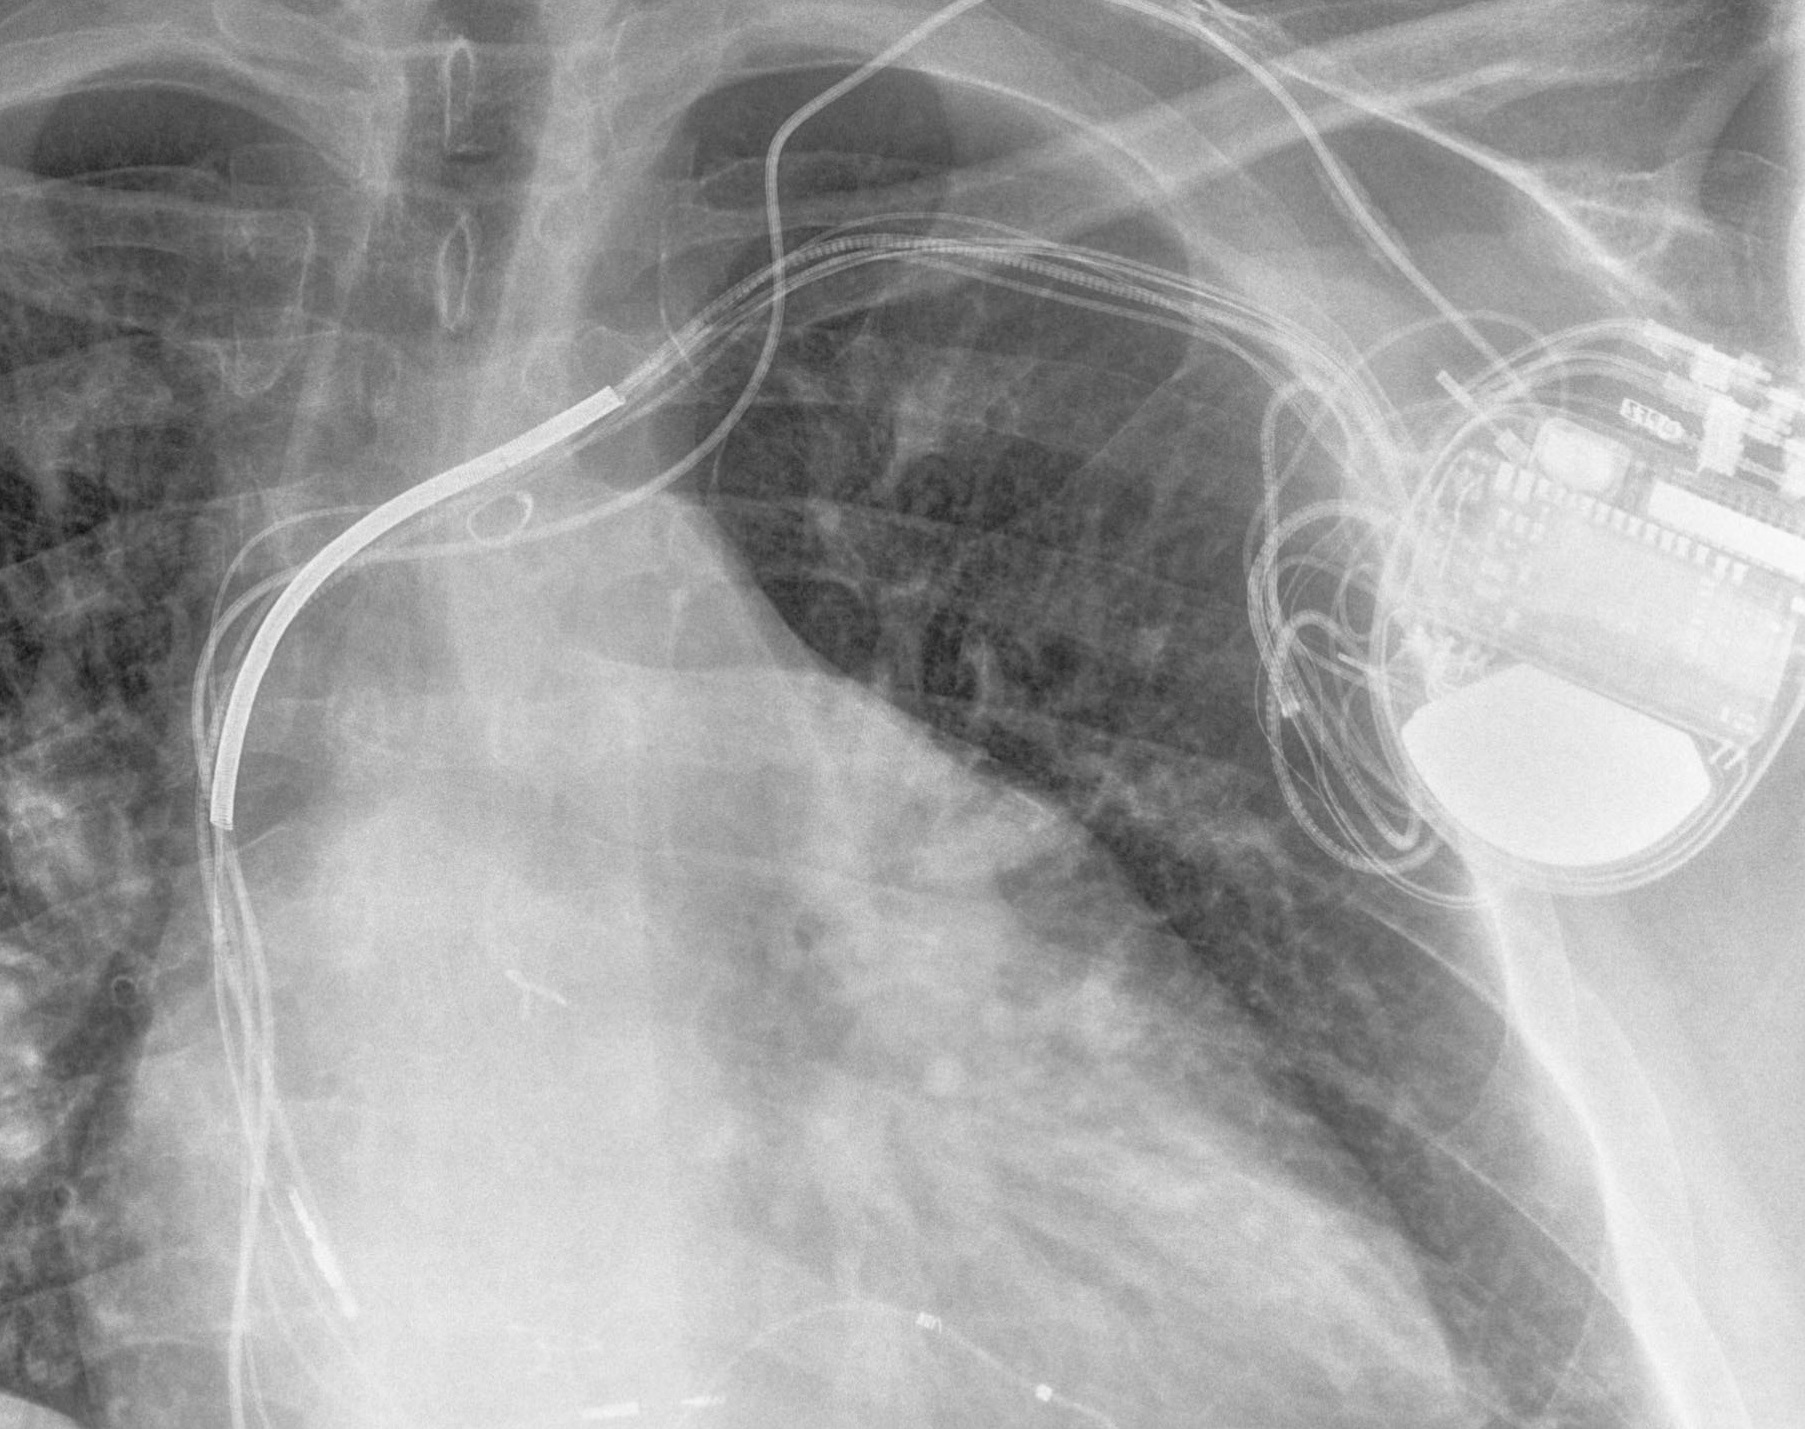

Electrophysiology and Pacing

Electrophysiology is a subspeciality that deals with heart rhythm problems. These can be rhythms that are too fast, too slow, or irregular. A simple procedure is performed to determine the mechanism for the heart rhythm abnormality with the aim of curing it with ablation. Cardiac implantable electronic devices (CIEDs) include pacemakers, defibrillators, cardiac resynchronization therapy and loop recorders. Pacemakers are used to treat slow heart rates. Defibrillators rescue high-risk patients from cardiac arrest. Cardiac resynchronization therapy improves function and survival in suitable heart failure patients. Loop recorders are used to continuously monitor heart rhythm to reach a diagnosis.